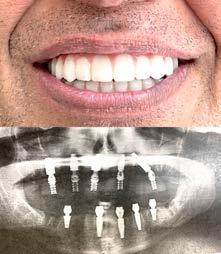

Одна из недавних операций:

Все-на-5-ти имплантах + несъемные зубы за 1 день

Высококлассные услуги по Зубной Имплантации в современной клинике, лимиторованной на установку имплантов.

* - установка 1 (одного) импланта не включая абатмент и коронку. Имплантация будет производится одним из специалистов клиники под руководством доктора Александра Антипова, челюстно-лицевого хирурга.

Цена указана для пациентов, оплачивающих наличными.

# 3 (2023) • 12 февраля Газета «Диаспора» – все о нас с вами ПО ВОПРОСАМ РАЗМЕЩЕНИЯ РЕКЛАМЫ ОБРАЩАЙТЕСЬ ПО ТЕЛЕФОНУ: (916) 487-9701 или (916) 705-0739 10 Замещение всех зубов на 4-х, 6-ти имплантах Одиночные импланты Несколько имплантов ИМПЛАНТАЦИЯ ЗУБОВ Установка одного импланта от FREE Consultation and CT-Scan